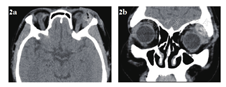

急诊入院者16例,均行眼眶CT检查,其中6例患者发现异物影(37.5%),发现异物影者主要为铅笔或筷子类异物(图1a、b),而竹子类异物较难发现,多表现为絮状密度影等感染征象、不能显示明显异物影(图1c、d);早期入院者7例,均行眼眶CT检查,其中4例发现异物影(57.1%),表现为条状或片状低密度影,周围伴软组织密度影(图2);中晚期入院者19例,4例在外院行了眼眶CT外余均在我院行眼眶CT检查,其中16例扫描表现为高密度条索状或片状异物影(84.2%),大部分能显出异物大致轮廓,周围多伴有软组织密度影(图3)。